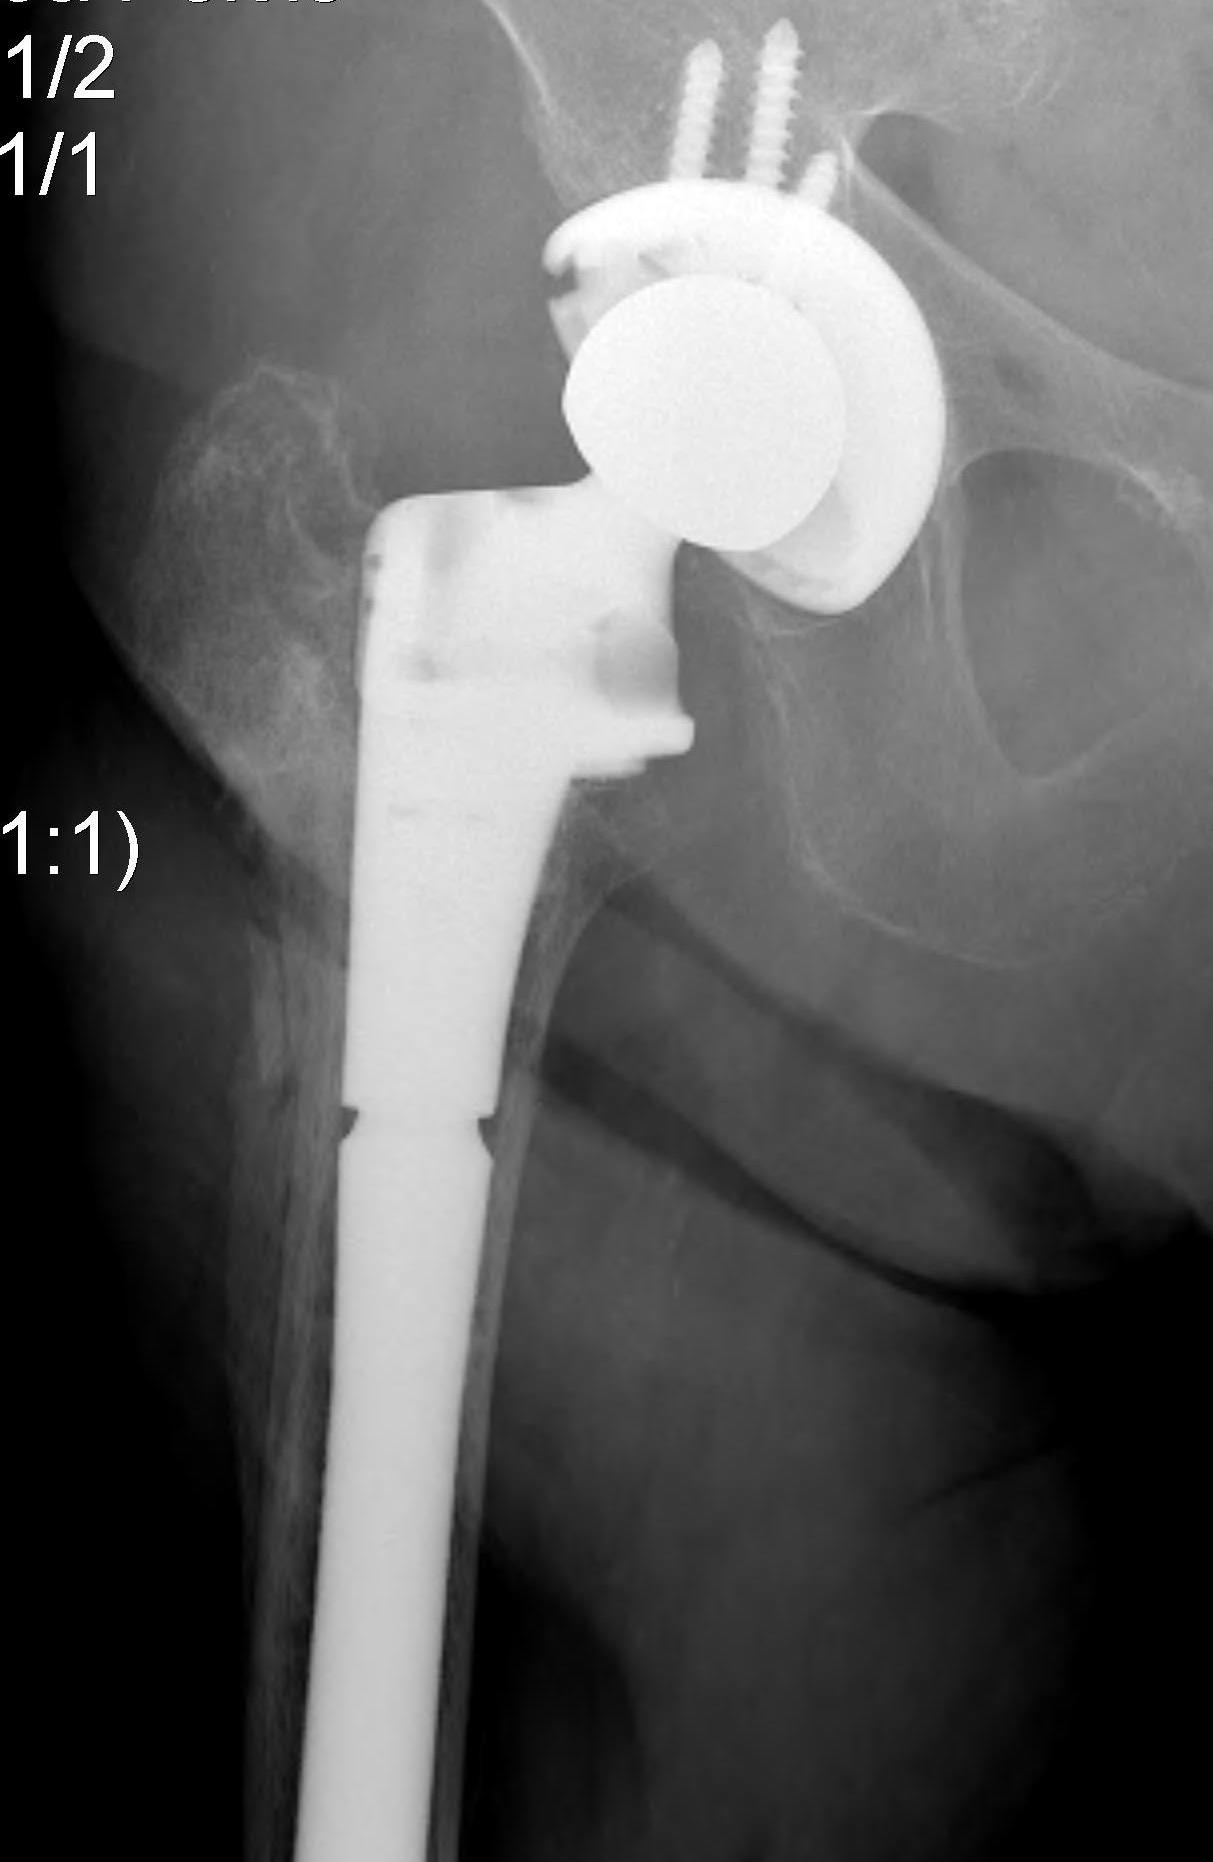

Hemiarthroplasty / Total hip replacement

Indications

- severe comminution

- salvage of failure of previous fixation

Technical

- may need calcar replacement

- may need greater trochanter fixation

D. Greater trochanter

- may need plate / cables to reduce